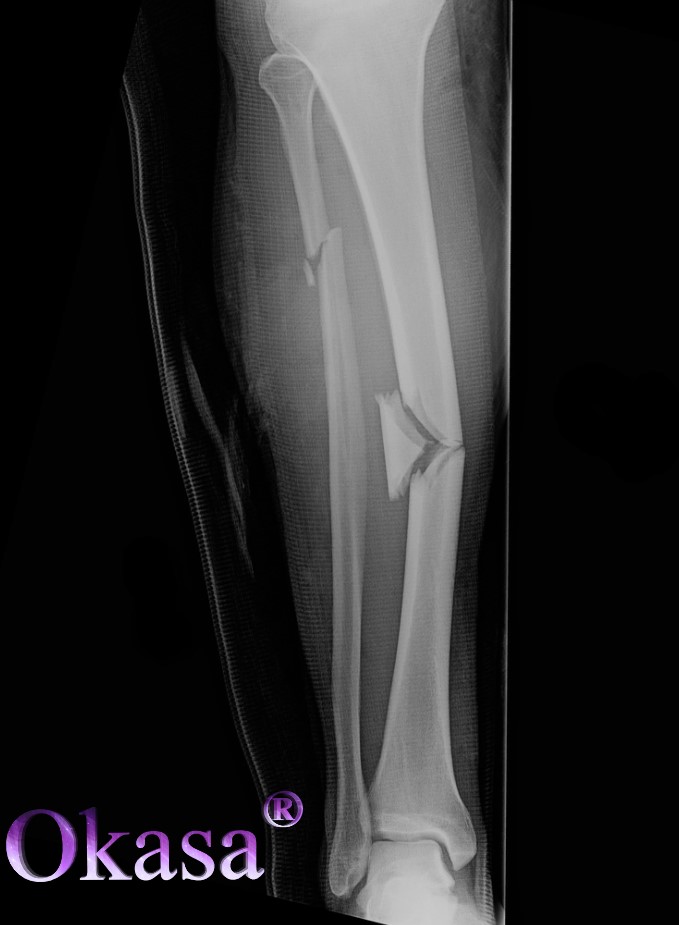

- Gãy xương do bị chấn thương: Chấn thương gãy xương do tai nạn giao thông chiếm tới 50% tổng số ca gãy xương. Ngoài ra, gãy xương do bị tai nạn lao động, do chơi thể thao, tai nạn trong sinh hoạt hàng ngày…

Triệu chứng khi bị gãy xương

Một số triệu chứng cơ năng của bệnh gãy xương là:

- Gặp các cơn đau: Người bị chấn thương dẫn đến gãy xương sẽ phải chịu các cơn đau, chỉ khi người bệnh bất động thì cơn đau mới giảm đôi chút.

- Triệu chứng giảm cơ năng: Triệu chứng này xuất hiện trong trường hợp gãy ít lệch hoặc gãy cành tươi.

- Trường hợp chi bị gãy rời sẽ khiến cơ năng mất hoàn toàn.